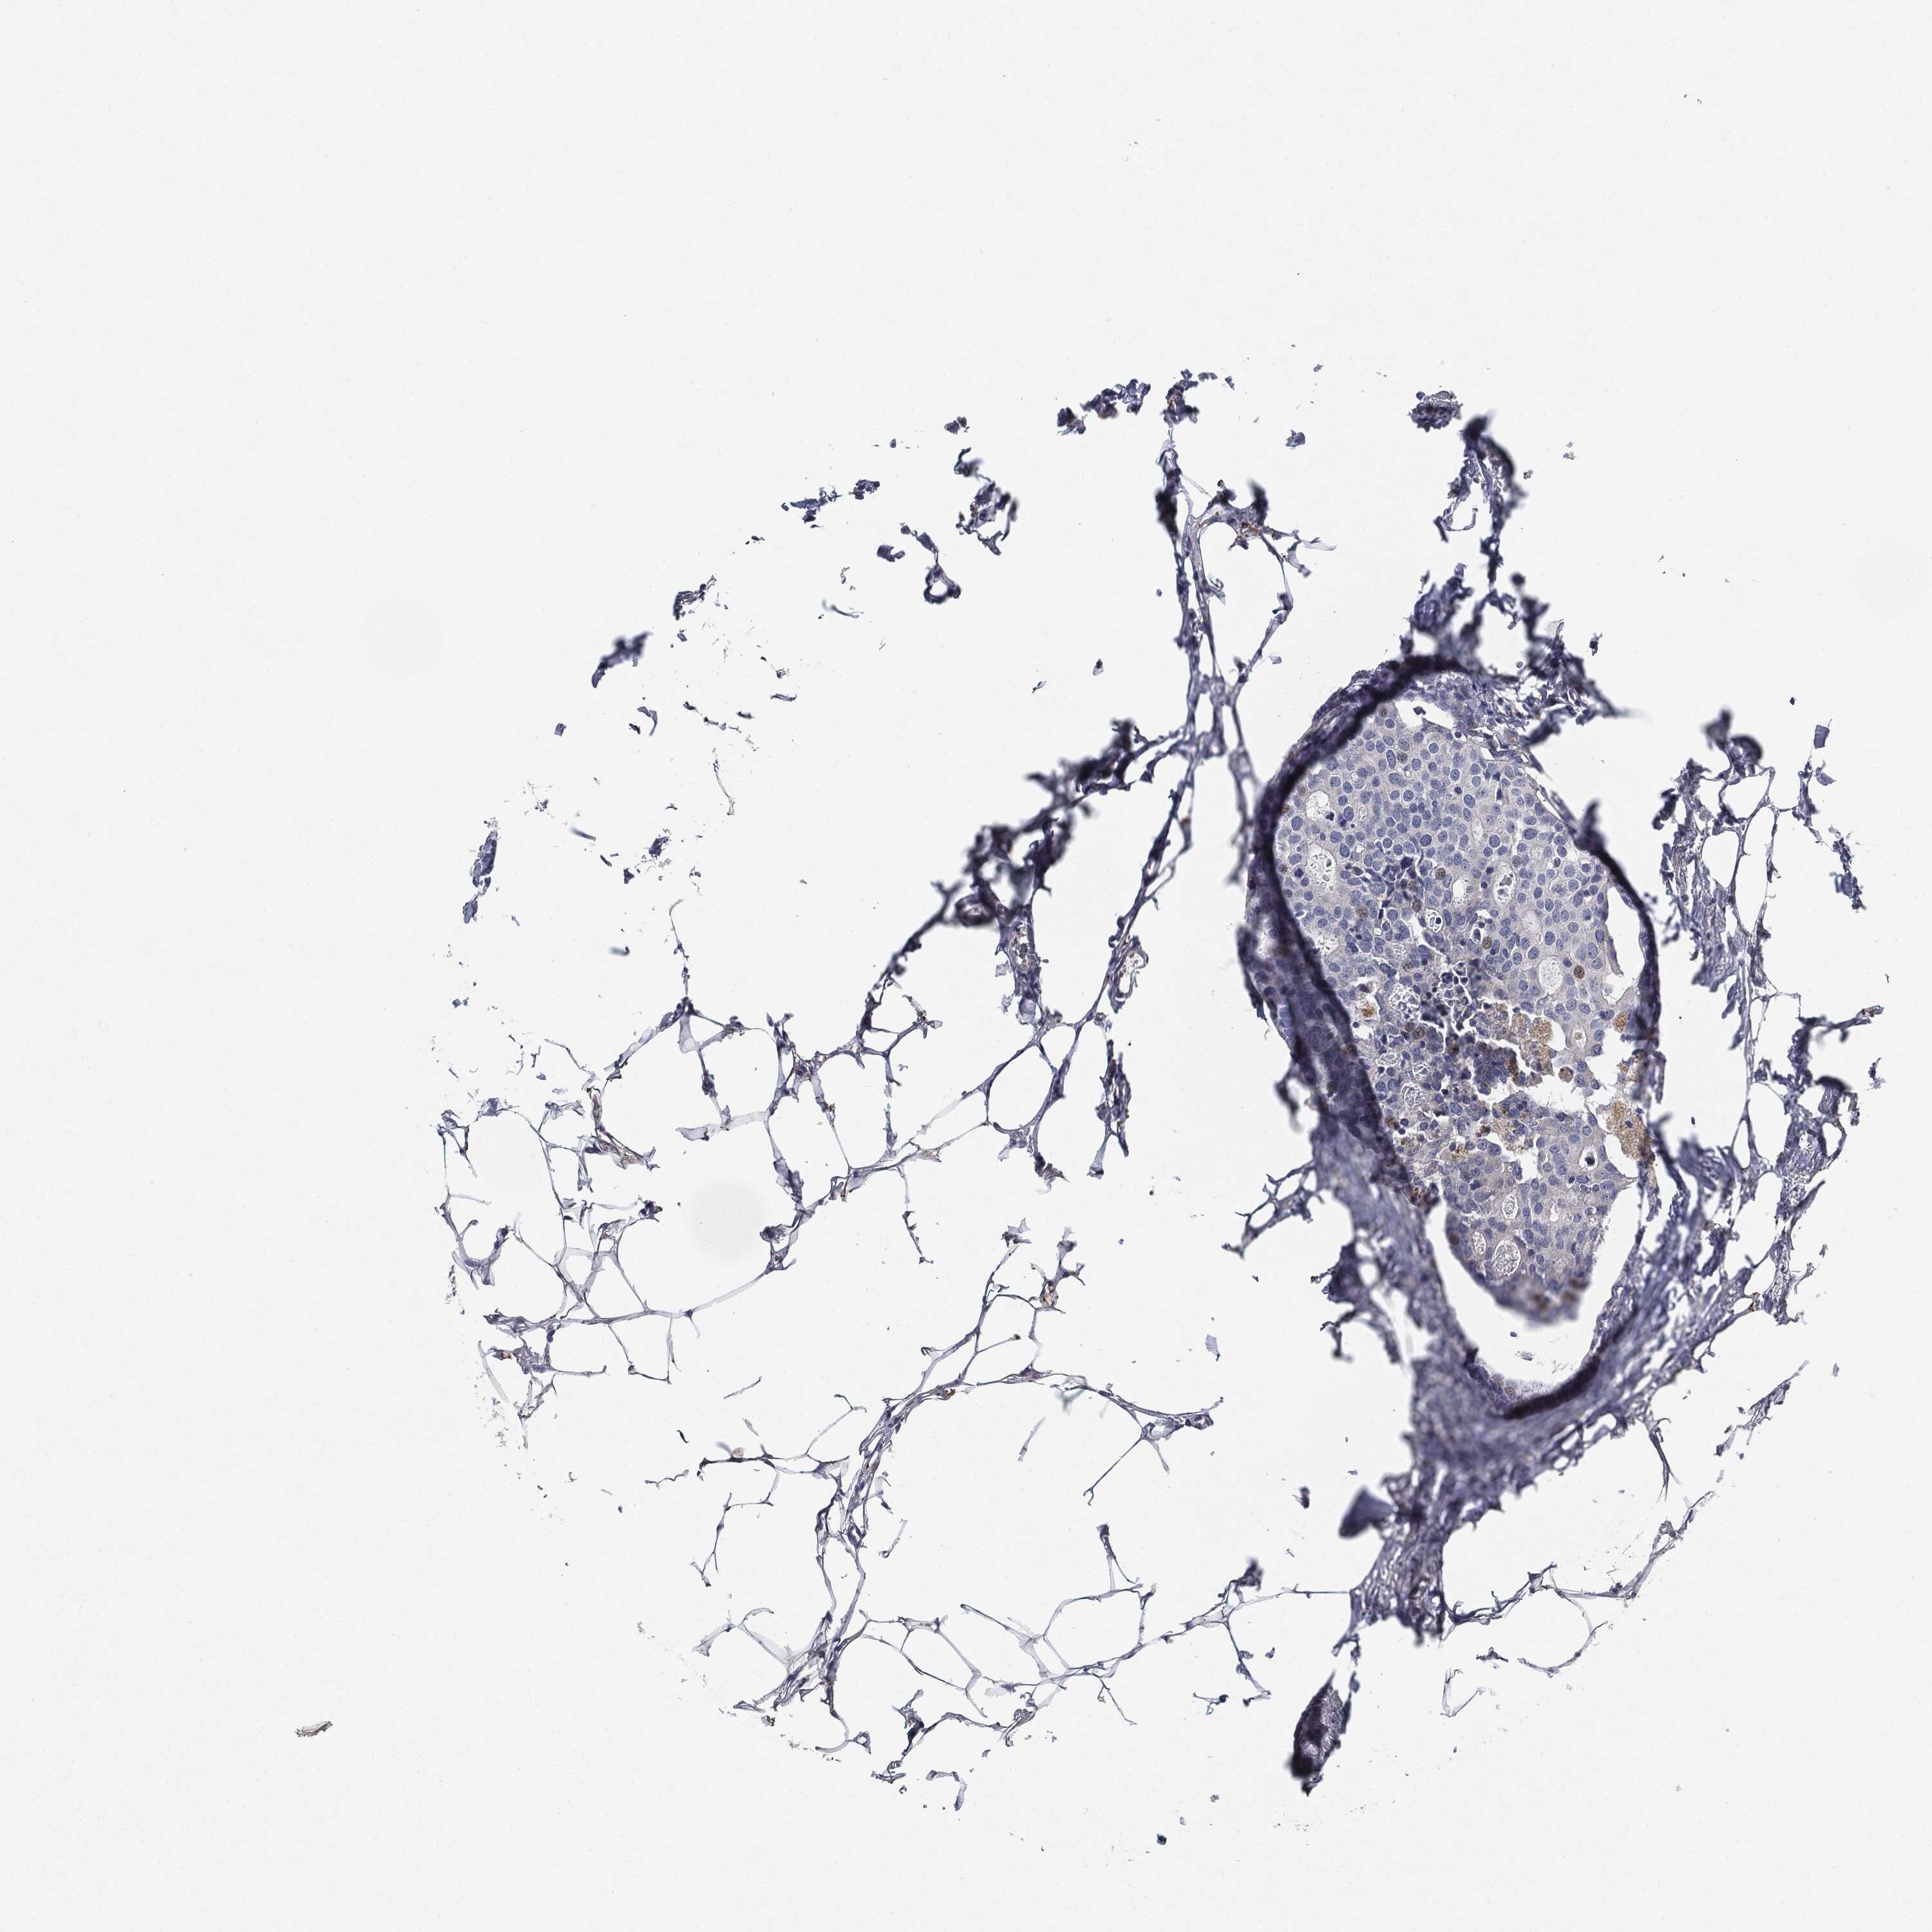

CANCER BREAST CANCER Show tissue menu

BRCA TCGA BRCA VALIDATION PROTEIN EXPRESSION

ANTIBODIES

AND

VALIDATION